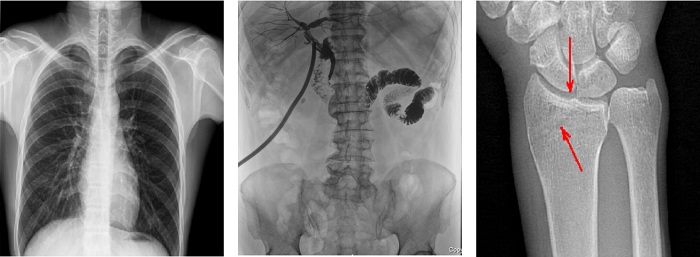

搭載100μm高品質(zhì)動(dòng)態(tài)平板探測(cè)器的普利德多功能懸吊動(dòng)態(tài)DR,不僅滿足常規(guī)的數(shù)字化X線全身攝影需求,同時(shí)還擁有數(shù)字?jǐn)z影、數(shù)字透視、數(shù)字造影、全景拼接等多種功能,極大地拓展了X線檢查在臨床應(yīng)用范圍,為醫(yī)院臨床應(yīng)用帶來更多實(shí)用價(jià)值?;诎傥⑵桨宓母咔宄上?,圖像清晰度與分辨率更高,可滿足不同檢查部位對(duì)細(xì)節(jié)成像的高品質(zhì)要求,在胸腹部、脊柱等復(fù)雜骨骼和軟組織的攝片上應(yīng)用,更便于觀察隱匿性病灶,精準(zhǔn)識(shí)別疑難病癥。

不同于靜態(tài)DR拍攝隱匿性病灶時(shí),由于組織重疊病灶難辨,耗費(fèi)時(shí)間更長且易漏診、誤診,普利德多功能懸吊動(dòng)態(tài)DR可通過動(dòng)態(tài)實(shí)時(shí)連續(xù)成像,對(duì)于重疊部位病灶或者易被遮擋的病灶進(jìn)行多角度動(dòng)態(tài)觀察,毫秒級(jí)時(shí)間內(nèi)實(shí)現(xiàn)動(dòng)靜態(tài)轉(zhuǎn)換點(diǎn)片,快速、精準(zhǔn)完成攝片。比如隱匿性肋骨骨折,可在透視下觀察患者的呼、吸過程,避開重疊影像,快速點(diǎn)片,保證檢查部位的病癥不被遺漏,實(shí)現(xiàn)精準(zhǔn)診斷。